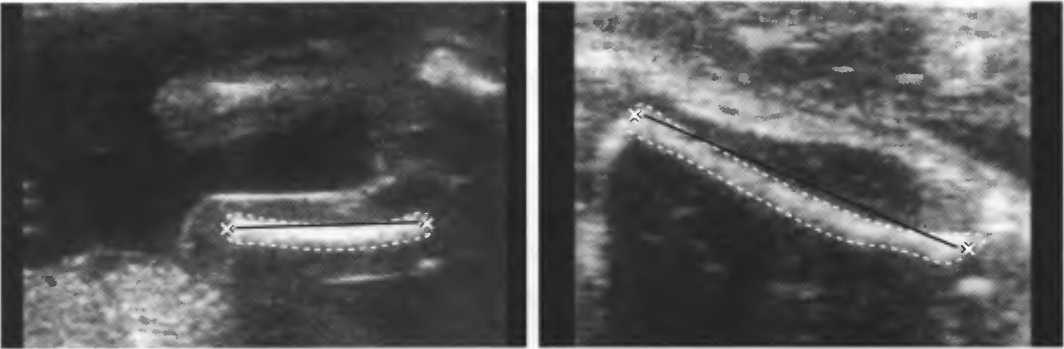

Рис.5. Два поперечных среза плода, демонстрирующих тень от позвоночника плода. Аналогичная тень от ребер может частично закрывать почки или печень. Изменяя угол наклона датчика, можно изменить положение тени таким образом, чтобы подлежащие ткани были видны отчетливо.

Неполное изображение

Артефакты в результате неполного изображения являются источником тревоги у исследователя, так как получается изображение только той части структуры, которая находится в плоскости сканирования. Так, при исследовании плода может визуализироваться только часть кости, а остальная часть может не попадать в плоскость. В результате, кость может выглядеть неполной или короче, чем она есть на самом деле (рис. 21а,б).

Рис.21а. Неполное изображение кости плода.

Рис.21б. В данном случае кость плода визуализируется полностью.